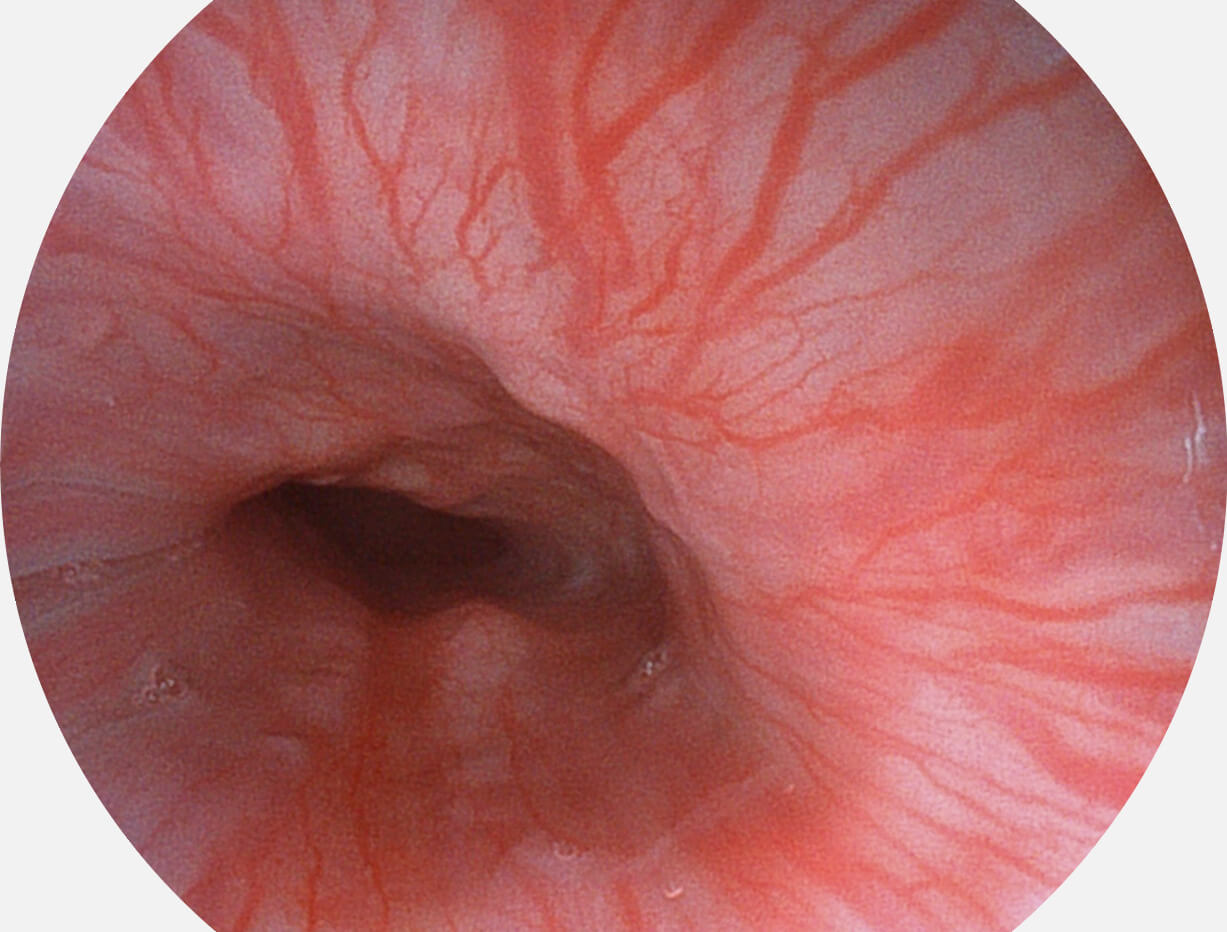

Spectral Focused lmaging, SFI

图像具有高亮度、高黏膜血管颜色对比度的特点,且不改变粘液、食物残渣、粪便的基本颜色,可在中远景下进行观察,助力消化道早期疾病的诊断。

白光图像

SFI图像